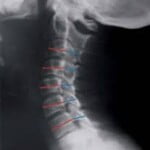

Muchos adolescentes llegan al consultorio con la solicitud o el resultado del mencionado estudio sin conocer generalmente el motivo del mismo. Por medio de una radiografía de la columna cervical con la tecnología adecuada, se trazan líneas que toman las medidas correspondientes, tanto de las vértebras cervicales como del canal medular, efectuándose un cociente conocido como índices de Torg y Pavlov, habitualmente informados en el estudio.